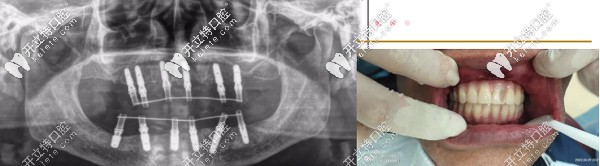

針對(duì)魏叔年齡大、口腔條件不佳的復(fù)雜特點(diǎn),熊小明院長(zhǎng)為魏叔定制ALL-ON-6即刻種植方案,拔掉剩余松動(dòng)殘牙,全口種植12顆,修復(fù)24顆牙。

▲魏叔種牙后

手術(shù)當(dāng)天,魏叔叔經(jīng)過(guò)消毒、麻醉、拔殘根、種植體埋入、放置基臺(tái)及裝牙冠等步驟,手術(shù)僅僅1個(gè)小時(shí)左右,魏叔缺失的牙齒得以“重生”,看著自己的新牙,高興得合不攏嘴。